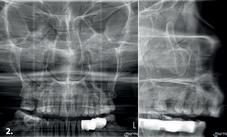

Maxillary sinuses

Frontal or left/ side view, with optimised trajectory